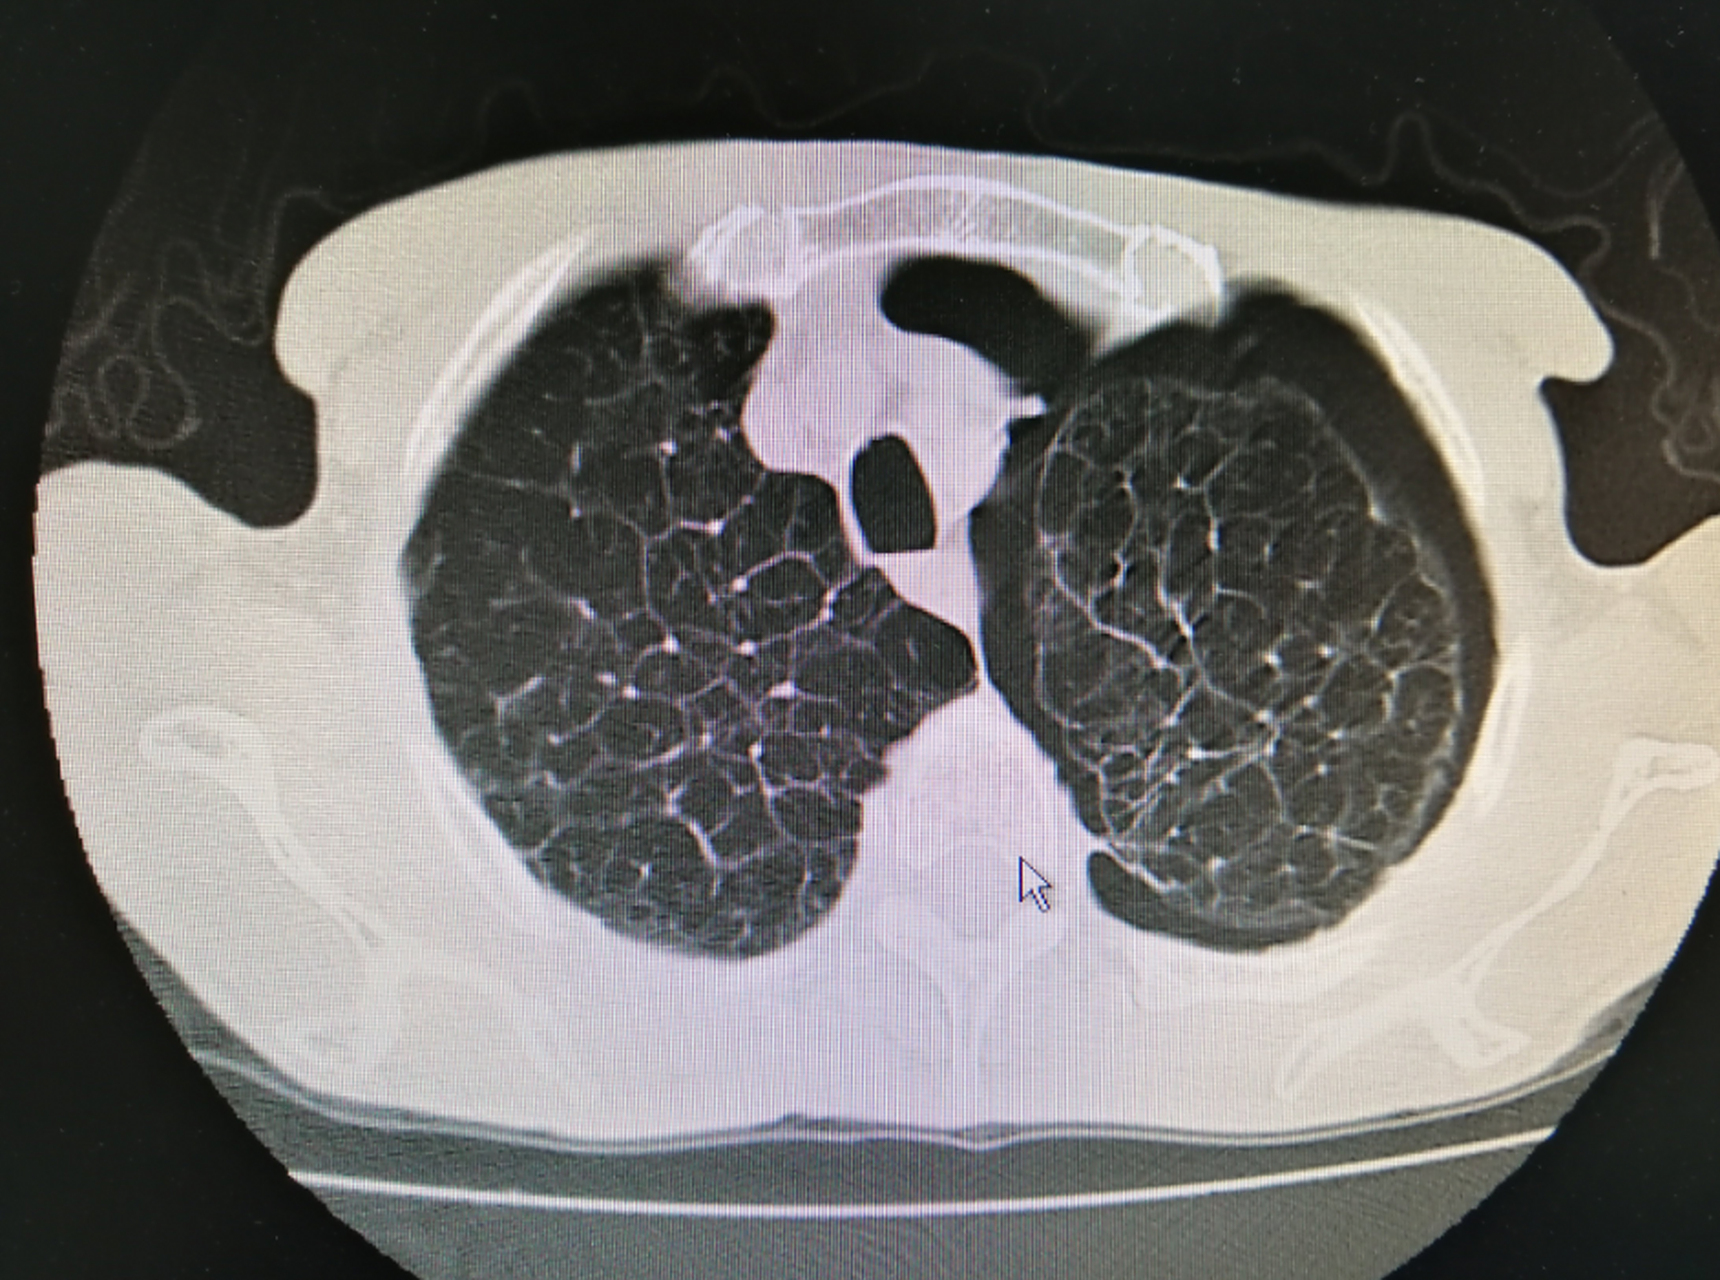

请问,这样胸部ct的表现,是肺气肿肺大疱前期的表现吗? - 丁香园论坛